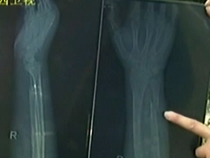

• 小腿骨折去医院 医腿未成险废手